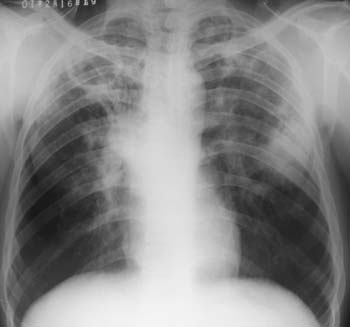

患者,男,46岁,发热咳嗽10余天,咯黄痰,时有痰中带血.

双侧胸廓大致对称,肺纹理稍重,右上肺可见圆形空洞,壁光滑,临近肺野内可见散在结节状高密度影,右肺门密度增高,形态变大,并可见有条索状高密度影与空洞连接,左上肺可见点片状,条索状高密度影,左中肺野内可见大片状高密度影,其中心密度稍高,边界清晰,形态不规则,临近可见小片状高密度影与之相连续,左肺上野内亦可见到类圆形稍高密度影,边界上清晰。

考虑: 双肺继发性肺结核(右上肺空洞形成) 左肺感染 建议必要时行ct检查,以进一步明确病变